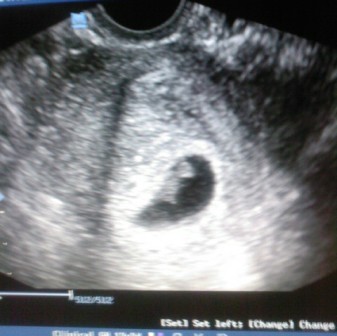

Csatolom a ma kapott képet:

CRL: 10 mm, petezsák: 35 mm, szívműködés kimutatható :D Doki szerint 6 hetes, szerintem 7. :) Majd kiderül... most nem saját dokimnál voltam, oda szerintem 2 hét múlva megyek.